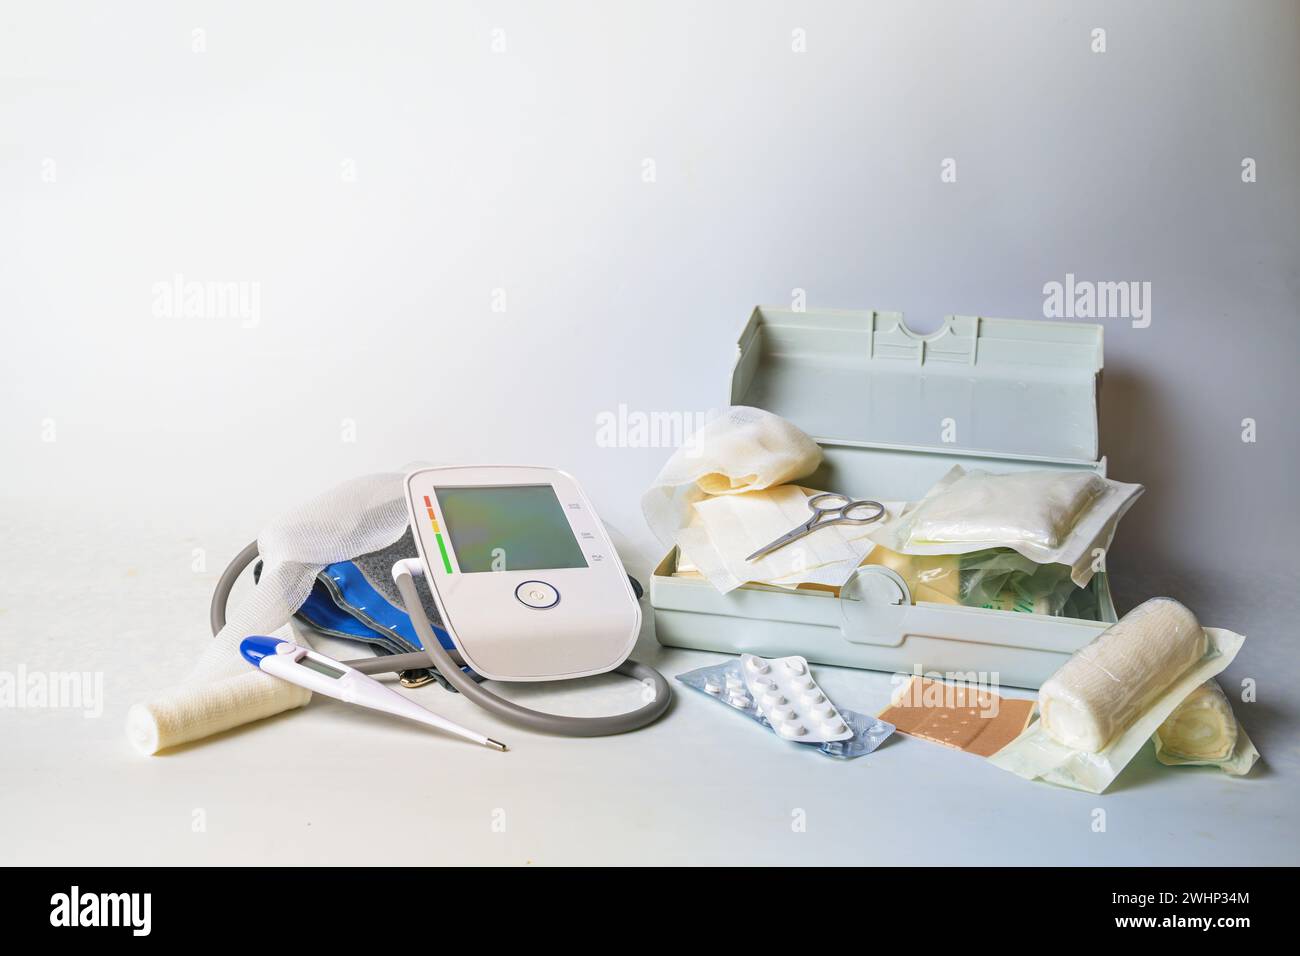

Important medical supplies for first aid and home medicine chest like blood pressure meter, fever thermometer, bandages, plaster Stock Photohttps://www.alamy.com/image-license-details/?v=1https://www.alamy.com/important-medical-supplies-for-first-aid-and-home-medicine-chest-like-blood-pressure-meter-fever-thermometer-bandages-plaster-image596087092.html

Important medical supplies for first aid and home medicine chest like blood pressure meter, fever thermometer, bandages, plaster Stock Photohttps://www.alamy.com/image-license-details/?v=1https://www.alamy.com/important-medical-supplies-for-first-aid-and-home-medicine-chest-like-blood-pressure-meter-fever-thermometer-bandages-plaster-image596087092.htmlRF2WHP34M–Important medical supplies for first aid and home medicine chest like blood pressure meter, fever thermometer, bandages, plaster